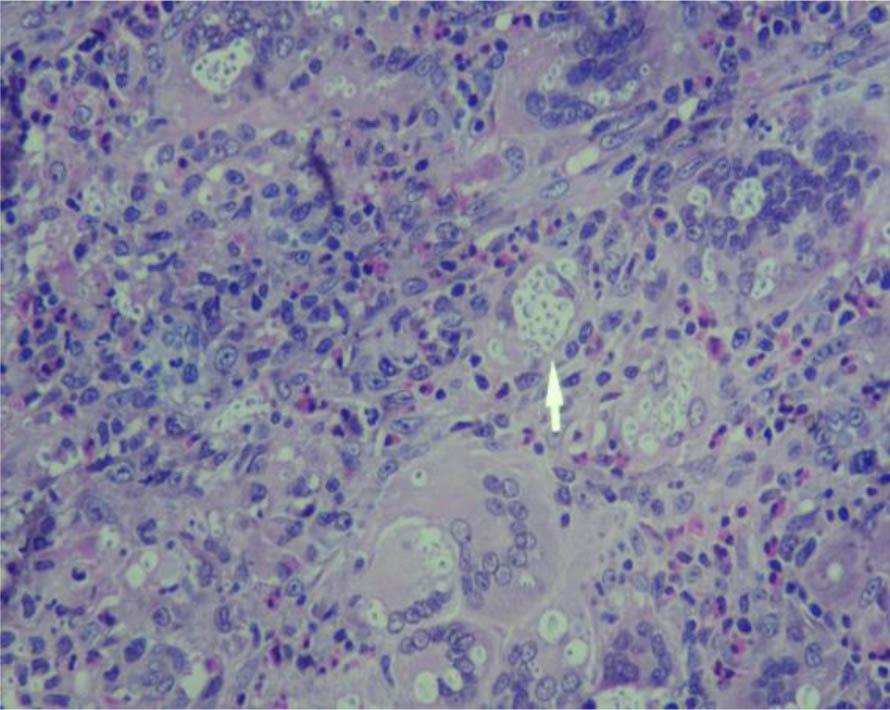

Figure 4